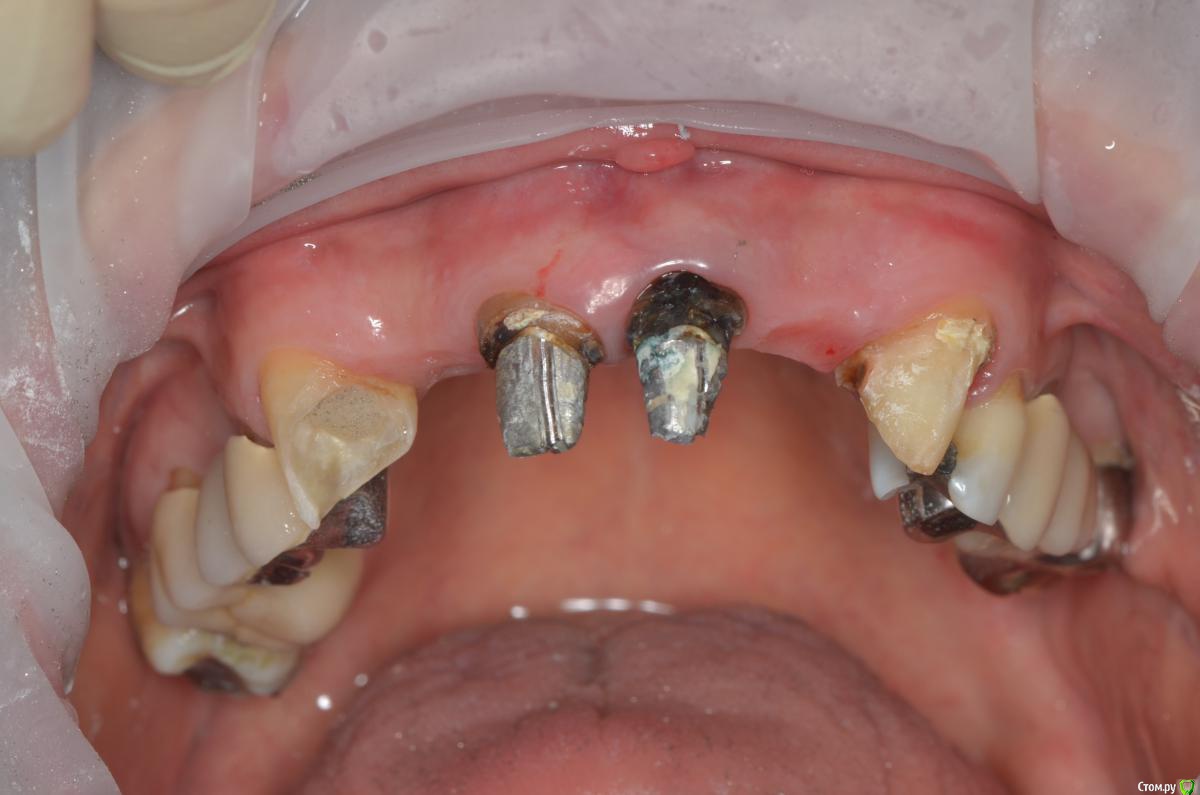

gangsta85 Опубликовано 27 сентября, 2016 Поделиться Опубликовано 27 сентября, 2016 Здравствуйте, уважаемые коллеги.Помогите пожалуйста разобраться.Центральные резцы в\ч были удалены и установлено 2 имплантата с пластикой десны, 12,22 отсутствуют в области 12 трансплантация слизистого лоскута.В тот же день изготовлены времянки по ключу с ваксапа. профиль трансгингивальной части сделан максимально под размер постоянной реставрации. 12,22 овоиды плотно прилегающие к десне.Вопросы:- Можно ли изготовить времянки сразу по форме максимально похожей на будущие реставраций и свести к минимуму коррекции профиля десны?- можно ли сделать надрез в области 22 и максимально погрузить в десну овоид 22, насколько плотно можно прижать овоид 11 в области слизистого трансплантата?- можно ли в такой ситуации добиться формирования десневых сосочков в области 12,22?-через какое время можно снять времянки для коррекции?- постоянная реставрация через 4 месяца? Что если снять слепок в день операции в лаборатории отфрезеровать времянки и установить через 1-2 дня , удастся ли в программе отмоделировать правильный профиль десны и овоиды? Как бы вы предпочли сделать времянки на CAD\CAM или в ручную? Ссылка на комментарий